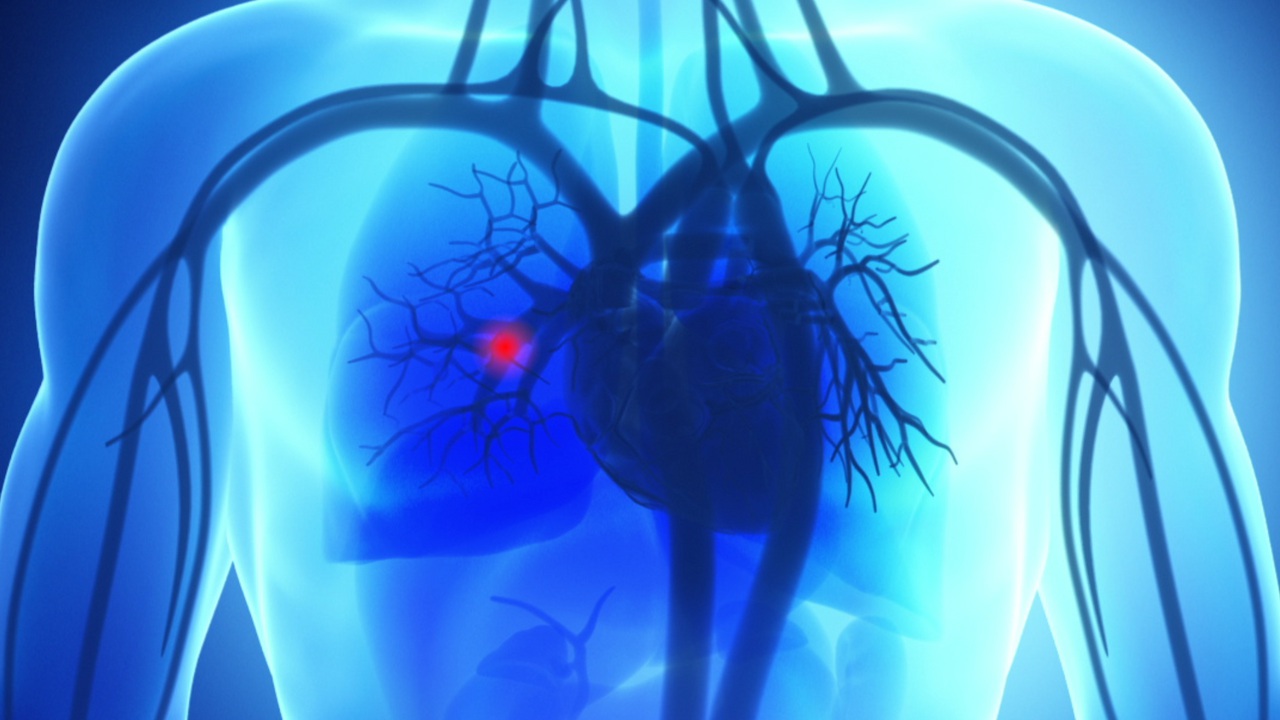

Pulmonary Embolism (PE)

This is a clog in an artery in your lung. It can happen suddenly, even in a healthy person. It's a serious medical condition that can be fatal.

A pulmonary embolism occurs when a tiny piece of debris travels through your bloodstream and gets stuck in an artery in your lung. In many cases, the debris is part of a blood clot that originally forms in a vein in your leg. That type of clot is called "deep vein thrombosis." But a pulmonary embolism can also be caused by other things. An air bubble. A piece of a tumor. A loose bit of marrow from a broken bone. Any of these can travel through your blood to your lungs and cause a blockage.